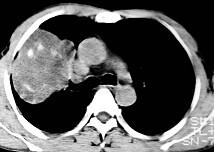

根据所提供的图像,选择最可能的诊断 ( )A.肺内软骨肉瘤B.胸膜间皮瘤C.球形肺炎D.机化性肺炎E.局限性不张

问题 根据所提供的图像,选择最可能的诊断 ( )

选项 A.肺内软骨肉瘤 B.胸膜间皮瘤 C.球形肺炎 D.机化性肺炎 E.局限性不张

答案 A